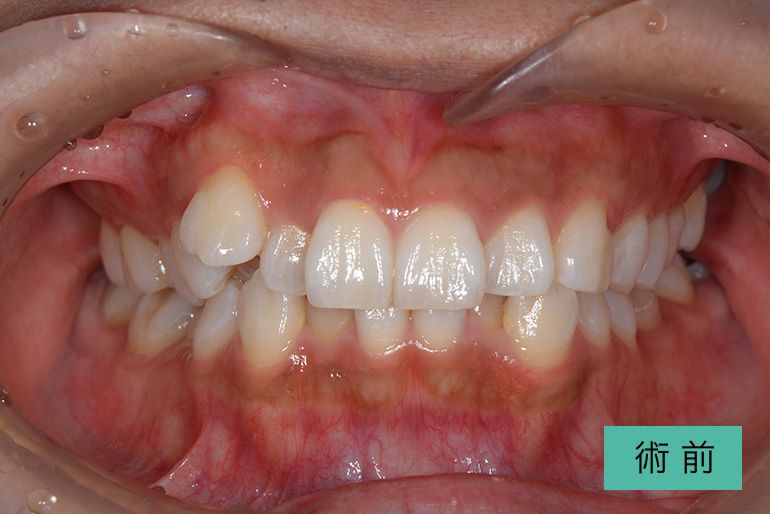

オールセラミック①

| 治療内容 | 上顎インビザライン矯正 右上1番から左上の2番のセラミック冠 上顎前歯の叢生、右上犬歯の捻転の改善のため、上顎のみインビザライン矯正を行なった また、根尖病巣があった為補綴を除去、顕微鏡根管治療を行い、セラミック冠を装着した |

| 治療期間・回数 | 約8ヶ月、15回(インビザライン矯正) 約4ヶ月、6回(補綴治療) |

| 費用(税込) | ¥275,000 (上顎インビザライン矯正) ¥495,000(165,000/1本)(補綴費用) ※自由診療 |

| リスク・副作用 | 疼痛、補綴物の脱落、咬合違和感、破折 |